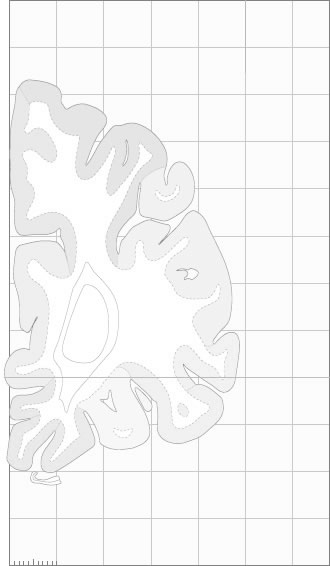

Frontal sections (Nissl) from the Atlas Brain:

Slice

Macroscopy

Schematic

Slice ID:

r1-0225

Plate NR:

04-05

Position:

-39,7 mm